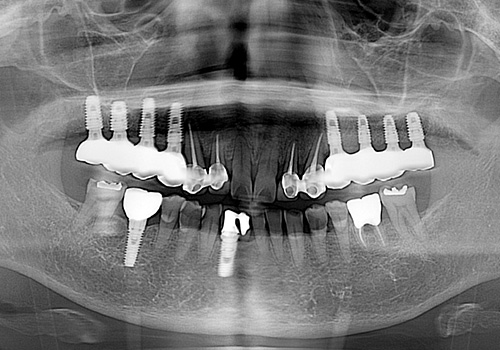

김○근님 임플란트 식립 전

2023년 2월

김○근님 임플란트 식립 후

2023년 6월 -